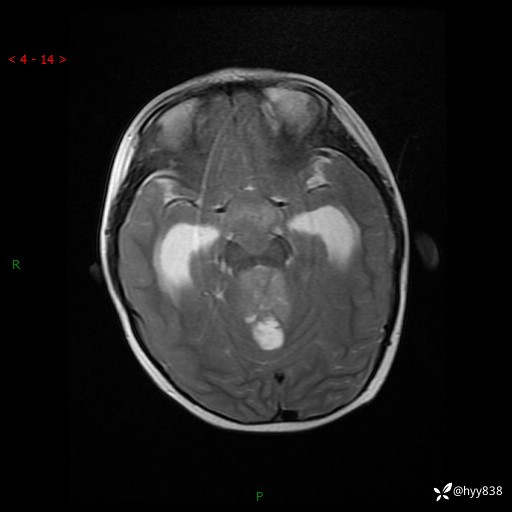

颅脑CT平扫

颅脑MRI平扫+增强

三脑室、四脑室多发病变,如何分析?